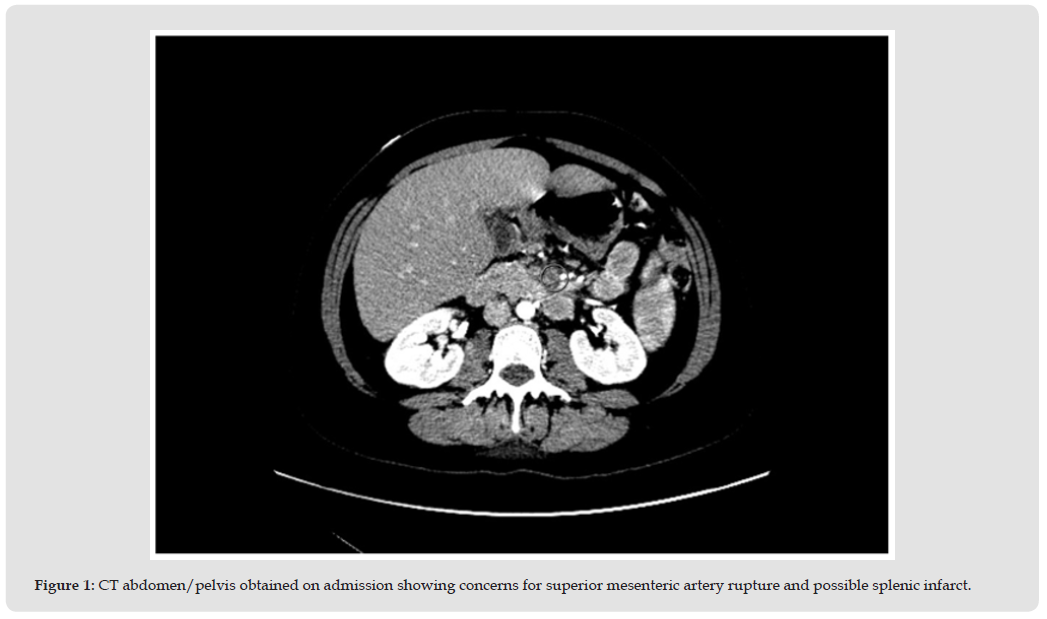

Our patient is a 37-year-old female with a known history of bicuspid aortic valve stenosis and ascending aortic aneurysm for which she underwent aortic valve replacement (AVR) and arch repair with 23 mm Medtronic Mosaic bioprosthetic valve and Gelweave graft. She presented to our institution with a three-month history of progressively worsening exertional shortness of breath and acute onset abdominal pain. CT imaging was concerning for superior mesenteric artery rupture and splenic infarct; (Figure 1) however, her abdominal discomfort was short-lived and conservative management was pursued. Given progressively worsening dyspnea on exertion, a transthoracic echocardiogram (TTE) was obtained. This revealed the presence of a vegetation on the aortic valve bioprosthesis in addition to moderate to severe aortic regurgitation; TTE images were also suggestive of aortic root abscess. (Figure 2). Admission electrocardiogram showed normal sinus rhythm in the setting of first-degree AV block and chronic left bundle branch block. (Figure 3) Blood cultures were obtained, and the patient was started on broad spectrum antibiotics including vancomycin and cefepime. Interestingly, the patient had been afebrile and hemodynamically stable throughout the admission. On admission, the patient had an elevated white blood cell count of 11,600 and a C-reactive protein of 12.6. Physical examination revealed a holosystolic murmur rated at 4/6 and a diastolic murmur at the left sternal border rated at 4/6. The patient did not exhibit any additional findings related to IE including Osler nodes or Janeway lesions.